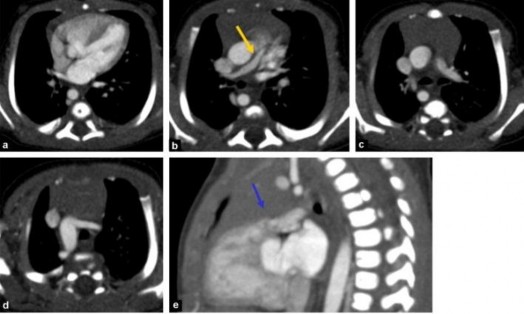

Hình 1.9. Chụp điện toán cắt lớp tim của bệnh nhân ToF nặng

Hình a: lỗ TLT và ĐMC cưỡi ngựa, hình b và c: thiểu sản nặng van ĐMP với thân ĐMP nhỏ, hai nhánh nhỏ, hình d: cung ĐMC quay phải, hình e: teo van ĐMP nhưng vẫn có vòng van và có hẹp phễu.

"Nguồn: Lapierre C., 2016" [58]